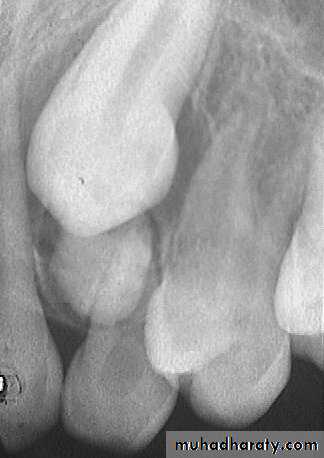

Ankylosed tooth: The tooth is in state of static retention, whereas in the adjacent areas eruption and alveolar growth continue.

Ankylosis of anterior teeth does not occur unless there has been trauma.

Diagnosis of ankylosed tooth:

1. Eruption has not occurred.

2. Alveolar process has not developed in normal occlusion.

3. The opposing tooth is out of occlusion.

4. Even with extensive root resorption, the tooth is not mobile.

5. Diagnosis by tapping with a blunt instrument.

6. Radiographically: A break in the continuity of the periodontal membrane.

Treatment of ankylosed tooth:

Early diagnosis is important.Treatment may involve surgical removal,

loss of arch length is evident, the dentist may choose to keep the tooth under observation.

The tooth that is definitely ankylosed may undergoes root resorption and be normally exfoliated.

Ankylosis of permanent teeth:

The incomplete eruption of permanent tooth may be related to a small area of root ankylosis.

The removal of soft tissue and bone covering the occlusal aspect of the crown should be attempted first.

Luxation technique effective in breaking the bony ankylosis.

If rocking technique is not immediately successful, it should be repeated in 6 months.